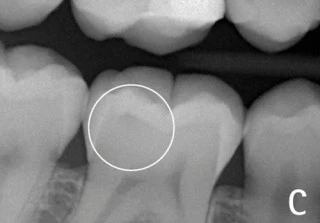

Hình 4: Vị trí tiếp giáp men-ngà (khoanh tròn) có sâu hay không sâu? Rất khó để nhận định trường hợp sâu mặt nhai mới đi qua lớp men răng chớm vào lớp ngà so với trường hợp không sâu răng nếu đánh giá trên phim X-quang tại chỗ.

Hiệu ứng mach band trong X-quang

nha khoa là ảo ảnh thị giác gây ra một vùng thấu quang giả nằm giữa hai cấu trúc có mật độ quang học khác nhau (gây ra mức độ cản quang khác nhau), ví dụ như men răng và ngà răng. Một đường mỏng nhìn thấy được ở bề mặt ngà răng và sâu răng có thể nhầm lẫn với nhau. Hiện tượng Mach band thông thường chỉ giới hạn là một đường mảnh 0.5mm dưới đường nối men-ngà (4).

Có thể thấy điều này rõ ràng hơn ở ranh giới giữa vật liệu phục hình (đặc biệt có chứa kim loại) nằm giữa men và ngà răng. Hiệu ứng này thường gây chẩn đoán sai thành sâu răng thứ phát hoặc làm nha sĩ đánh giá sai về độ lớn của tổn thương sâu răng. Nó cũng gây chẩn đoán thiếu trong trường hợp gãy chân răng theo chiều ngang do sự khác biệt về cường độ tia (radiographic intensities) của răng và xương. (5)